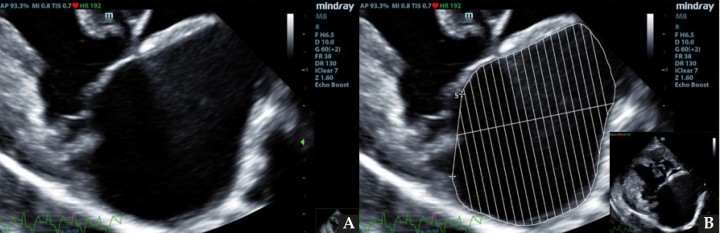

Se realizó la medición del volumen del atrio izquierdo con el método monoplano sumatorio de discos (MOD)9 a partir de la técnica de Simpson, que consiste en la medición del volumen del AI mediante la suma de los volúmenes de diferentes discos contiguos perpendiculares al eje mayor del AI generados por el software del ecógrafo, tras trazar el área del AI y su eje mayor de forma manual. Esta medición se realizó desde el corte paraesternal derecho longitudinal de 4 cámaras en telesístole, previo a la apertura de la válvula mitral (Fig. 1). Se siguió el borde endocárdico del atrio izquierdo, previo a la apertura de la válvula mitral en la telesístole cardíaca, sin incluir las venas pulmonares. Posteriormente, lo correlacionamos con el peso del paciente realizando la ratio: LAv/BW = volumen del atrio izquierdo (ml) / peso del paciente (kg).1,2,6

Figura 1

ECDM. (A) Medida mediante MOD del volumen del AI. (B) Corte paraesternal derecho 4 cámaras, zoom AI. Ratio LA/BW = 3, 8 ml/kg.